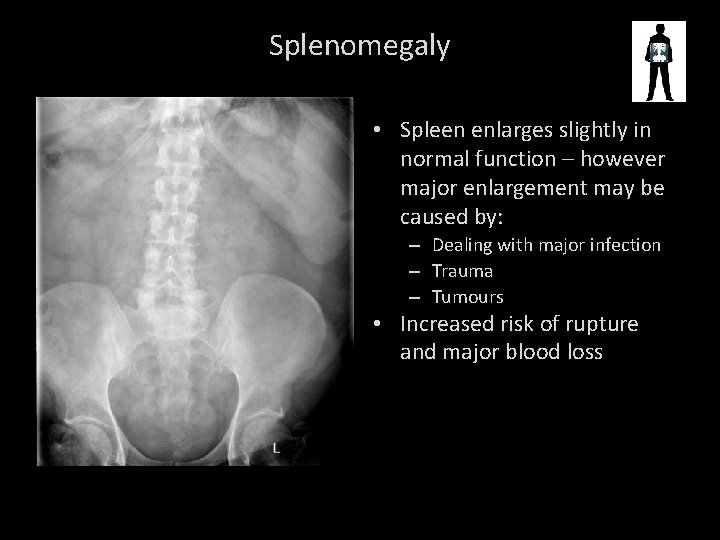

SPLENOMEGALY

Splenomegaly • Spleen enlarges slightly in normal function – however major enlargement may be caused by: – Dealing with major infection – Trauma – Tumours • Increased risk of rupture and major blood loss